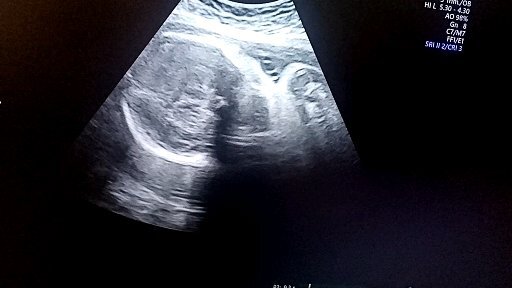

Узи , 1 плодный мешок такого то размера ,расположен так-то так. Ну ок зафиксировали точно беременна. На учет вставать ближе к 8 неделе, когда забьется сердце. Счастливая ушла.Теперь я не одна нас 2,питание сон, витамины .Витамины со времен ЭКО я знала лучшие Фемибион 1,дальше 2.